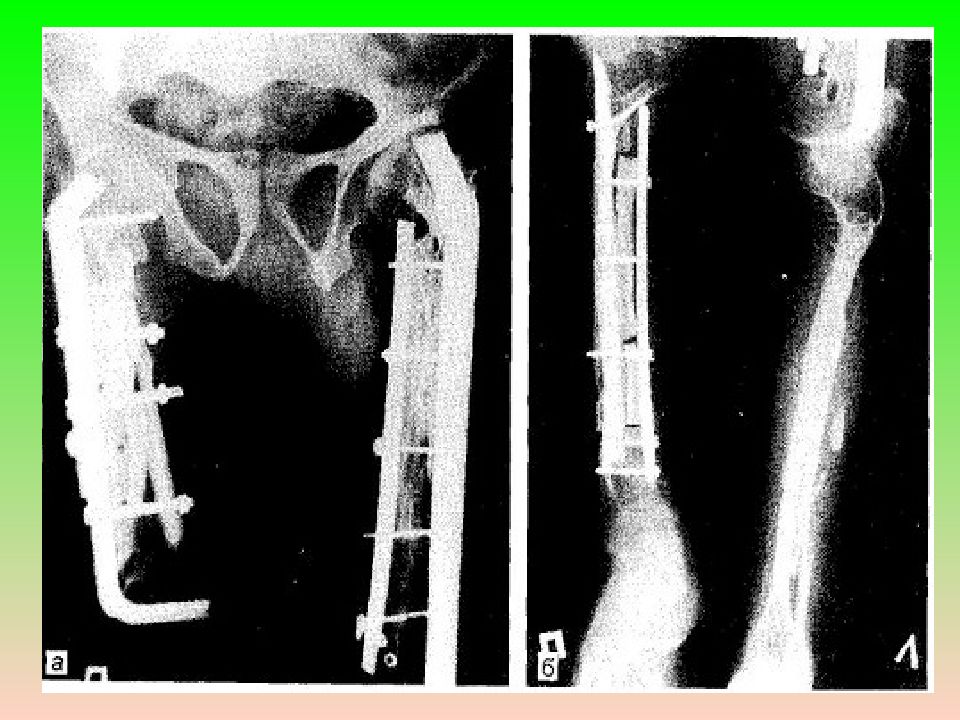

Слайд 15: Лечение

Краевая резекция кости с последующей пластикой дефекта. При выраженных деформациях костей, краевая резекция должна сочетаться с корригирующими остеотомиями с накостным или внутрикостным остеосинтезом.

Слайд 16